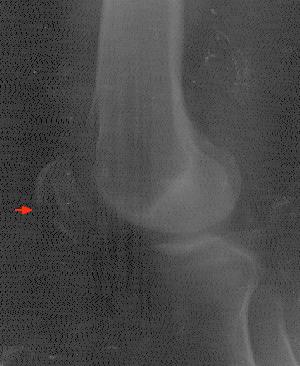

Eine kleine Unachtsamkeit - wohl begünstigt davon, daß gerade ein Hagelschauer niederging - führte dazu, daß ich gestolpert bin, und dummerweise stürzte ich exakt mit dem Knie auf eine Bordsteinkante. Zunächst konnte ich mit gestrecktem Knie noch laufen und auch Ein- und Auskuppeln beim Autofahren funktionierte bei vorsichtigen Bewegungen schmerzfrei. Doch am Hotel in Falkirk wurden die Schmerzen schlimmer und es wurde klar, daß wohl doch ein größerer Schaden vorliegen müsse. Daraufhin erfolgte ein Auf Details der Heimreise soll hier nicht weiter eingegangen werden, seit dem 6.1. werde ich jedenfalls in der orthopädischen Fachklinik in Wetter behandelt, wo am 7. im Rahmen einer Operation eine Fixierung der Kniescheibe mit einer Art Drahtkäfig erfolgte. Insgesamt wird der Klinikaufenthalt wohl etwa zwei Wochen dauern, die vollständige Rehabilitierung ungefähr zwei bis drei Monate. Spätestens dann - hoffentlich schon eher, was sich noch zeigen wird - sollten wieder Spielbesuche drin sein. Vorher - aber eben nicht, wie angekündigt, in den nächsten Tagen, sondern erst nach Beendigung des Klinikaufenthalts - werden Berichte und Fotos zu den im UK besuchten Spielen folgen. Da ich im Krankenhaus nicht nur auf einen Internet-Zugang verzichten muß, sondern auch auf einen Computer, ist das anders nicht machbar. Dieser Bericht wurde handschriftlich verfaßt und von meiner Frau Almut - bei der ich mich nicht nur dafür, sondern auch für die generelle Unterstützung beim Betreiben dieses Angebots ganz allgemein und bei der Bewältigung der aktuellen Krise ganz ausdrücklich bedanken muß. Ihr werdet nach meiner Entlassung aus der stationären Behandlung zumindest im Rahmen der Berichte und Fotos bis zum 2.1. von mir hören, und früher oder später geht es dann ja auch mit ganz neuen Spielen weiter! Bis dahin wünsche ich Euch alles Gute - und macht das hier Beschriebene nicht zuhause nach... ANSGAR |